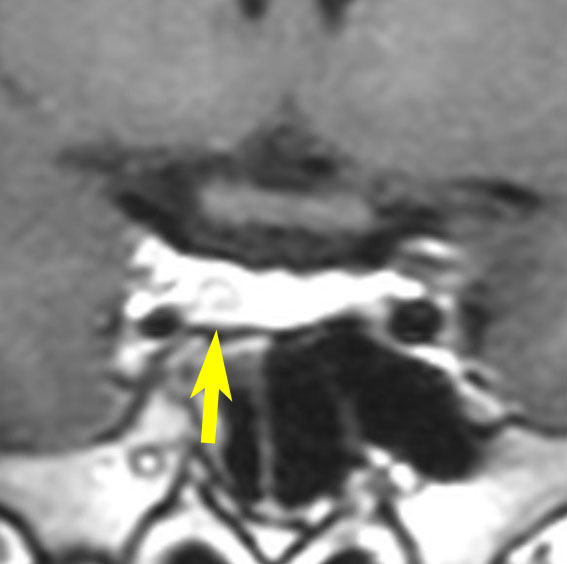

典型的なMRIの画像です

下垂体腺腫のMRIです。両側の視野障害(両耳側半盲)のために手術を受けた患者さんのものです。この腫瘍は非機能性腺腫といってホルモンを出さない腫瘍でした。少し大きめでしたが全部取れて視野の障害はよくなりました。

左の2枚はガドリニウム造影剤を使って写したもので腫瘍の形がよくわかります。右の1枚はT2強調画像と言います。MRIでは撮影の仕方によって見え方が違います。